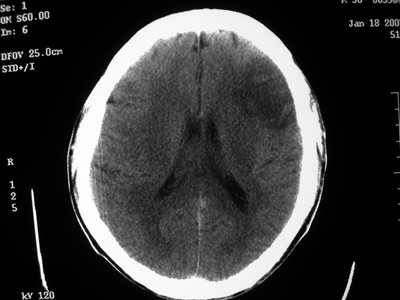

以下是引用卜一在2007-1-19 15:29:00的发言:[br]治疗前:1月14日右侧额叶皮质下低密度影,而治疗后:1月18日右侧阴影消失,新近出现左侧额叶侧脑室前角旁大片状低密度影,边缘模糊。支持—双侧额叶后部缺血性脑梗塞。